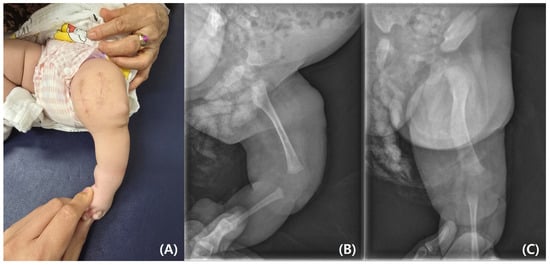

The parents requested rapid resection of the bifid femur with aggressive treatment. At the age of 4 months, surgical excision of the left bifid femur was performed (Figure 4 and Figure 5). The bony protuberance of the distal femur was resected through an anteromedial incision. After resecting the bone, a tented, hard skin lump remained. While making another incision to resect the remaining skin, we found what appeared to be the cartilage cap, which was subsequently removed. The resected femur was sent for pathological examination, and the results showed no specific abnormalities. The patient’s course of recovery at the hospital was uncomplicated, and she was discharged on postoperative day 2. She was subsequently scheduled for follow-up care after discharge, including wound management and suture removal.

Figure 5. (A) Postoperative photograph. (B) Postoperative lateral and (C) anteroposterior radiographs.